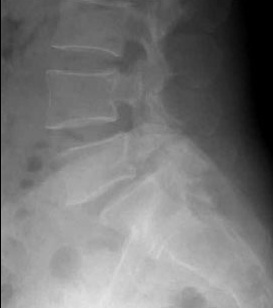

척추분리증이란 척추 후관절 위 협부에 결손이 생기는 병으로 쉽게 말하자면 척추뼈에 금이 가 척추뼈가 벌어진 상태를 말한다. 척추분리증이 더 진행되면 척추체가 어긋나게 되는데 이러한 경우에는 척추분리증이라 하지않고 척추전위증이라고 한다.

그러나 척추분리증은 초기에는 통증이 없었더라도 점점 시간이 지남에 따라 허리뼈가 앞으로 미끄러지면서 진행되는 경우가 많기 때문에 날이 갈수록 허리에 통증이 심해지기 시작한다.

그러나 이러한 물리적인 요법의 치료로 인하여 통증이 없어졌다고 그냥 방치해두거나 계속 과격한 운동을 하게 되면 척추뼈가 점차 앞으로 미끄러지거나 더 어긋나는 ‘척추전위증’으로 이어질 수도 있다.